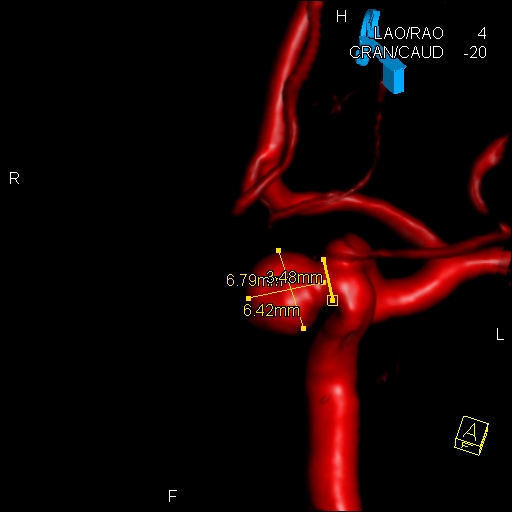

Norma Wooley's aneurism was 6.42 mm. across. Photo: Loyola University Health System

Wooley's aneurism was roughly one-fourth inch across, and shaped like a gumball. It could burst at any time and cause a debilitating or fatal stroke. Her clinical presentation was suspicious for what's called a "sentinel hemorrhage," in which an aneurism on the brink of rupture will often perforate without catastrophic clinical or radiographic findings. One day at work, Wooley began slurring her words, as if she had been drinking. Her mouth and eyelid drooped, and she had a headache that felt like someone was hitting her on the back of her head with a baseball bat. An ambulance took her to a local hospital, and she was transferred to Loyola.